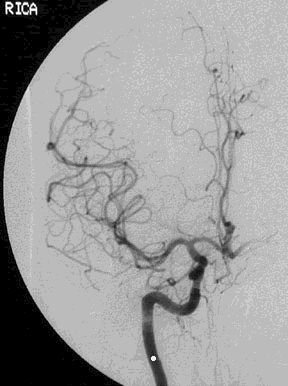

| The process of embolization is demonstrated here. Emboli are most likely to go to the middle cerebral arterial circulation, but other places are possible. Embolic infarcts may be hemorrhagic, because the embolus may not completely occlude the artery. |